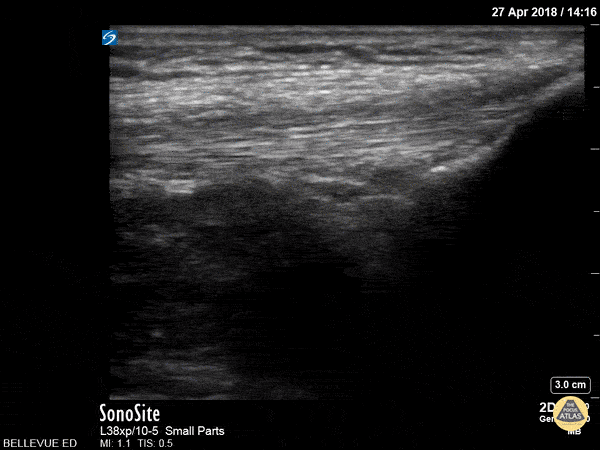

This clip shows the quadriceps tendon in longitudinal axis. It is hyperechoic, linear and fibrillar in texture. The distal tendon inserts onto the proximal patella, seen on the right side of the screen at the beginning of the clip. As the probe is moved proximally, the quadriceps muscles are seen deep to the tendon. Hannah Kopinksi and Dr. Lindsay Davis - NYU Emergency Medicine